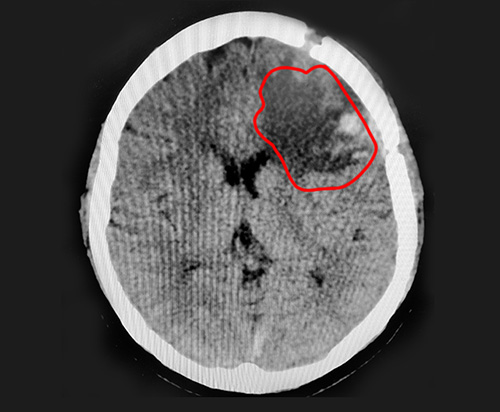

▲术后CT复查影像,巨大脑膜瘤已切除

术后CT复查影像中,巨大的脑膜瘤已被切除。患者乐观开朗的性格,也对其术后恢复起到了良好的推动作用。